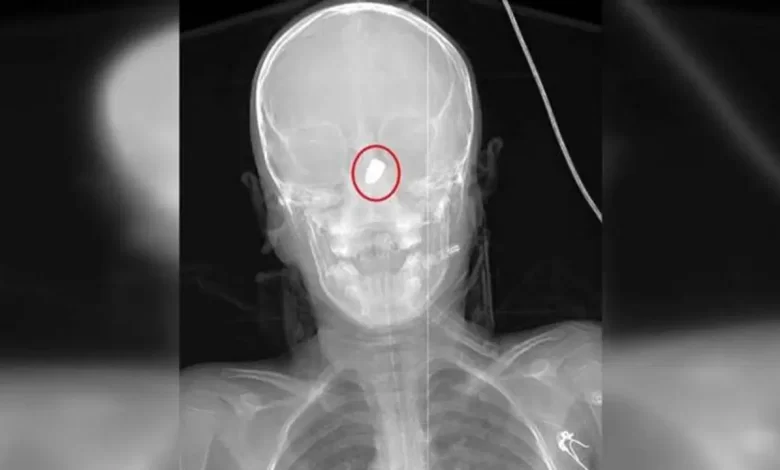

Şanlıurfa’nın Suruç ilçesinde 1 Haziran’da parkta bisiklet sürerken başına yorgun mermi isabet eden Sami Yusuf Kaya (6) ile 11 Haziran’da Antalya’nın Kepez ilçesinde konutunun bahçesinde göğsüne yorgun mermi isabet eden Suriye asıllı Abdurrahman Omar, hayatını kaybetti. Son olarak Adana’da 7 Haziran’da hobi bahçesinde karnına yorgun mermi isabet eden fotoğraf öğretmeni Burak Ateş (36) ile 9 Haziran’da sipariş hazırladığı sırada başına yorgun mermi isabet eden döner ustası Ramazan Malgir (39), yaralandı. ÇÜ Tıp Fakültesi Balcalı Hastanesi Acil Tıp Anabilim Kolu Lideri Prof. Dr. Ahmet Sebe ve Adana Kent Hastanesi Beyin ve Hudut Cerrahisi Kısmı’ndan Doç. Dr. Ali İhsan Ökten, son devirde çok sık gündeme gelen yorgun mermi olaylarıyla ilgili konuştu.

Prof. Dr. Ahmet Sebe bilhassa yaz aylarında düğün mevsiminin de başlamasıyla birlikte bu hadiselerin hem çocuk hem yetişkin acilde sıklıkla görüldüğünü söyledi. Yılda yaklaşık 20-25 kişinin yorgun mermi kaynaklı acil servislerine başvurduğunu belirten Prof. Dr. Sebe, bu hadiselerin bazısının yapılan tetkiklerde tesadüfen tespit edilebildiğine dikkat çekti. Prof. Dr. Ahmet Sebe, “Bizim vatandaşlarımız silah sesi duyduğunda balkona, pencereye koşuyor. Bunun yerine gizlenmeyi, kendini muhafazaya çalışması gerekir. Silah sesi duyduğunuzda balkona, pencereye koşmayın; gizlenin. Birçok vakit yorgun mermi fark edilmiyor, anlaşılmıyor. Tesadüf yapıtı bulduğumuz hadiseler da oluyor. Kişi balkonda otururken bir bakıyorsunuz yere yığılmış. Güya bir inme ya da beyin kanaması geçirmiş üzere görünüyor. Fakat hastaneye geldiğinde çekilen görüntülemelerde bunlar ortaya çıkıyor. Yorgun mermi kol ve bacak üzere uzuvlara geldiğinde hastaneye ulaşmalarında çoklukla bir düşünce olmuyor lakin beyin, kalp ya da karın içindeki bir organa geldiğinde hastalar acile ulaşamadan hayatını kaybedebiliyor. Birinci yardım uygulaması olarak bası yapılabilir lakin iç organlara geldiyse kişinin yapacağı en hakikat şey, 112 Acil Davet Merkezi’ne haber verip bir an evvel hastayı sıhhat kuruluşuna ulaştırmaktır. Buraya ulaştığında ise hastanın durumuna nazaran beyin cerrahi, göğüs cerrahi, genel cerrahi ya da girişimsel radyolojiye yönlendirerek, tedavisini gerçekleştiriyoruz” diye konuştu.

Doç. Dr. Ali İhsan Ökten de “Yorgun mermi, beynin sessiz bölgelerine geldiğinde çok fazla hasar yaratmayabilir. Lakin beynin derin bölgelerine hakikat gitgide orada damar yapıları da ağır olduğu için beyin kanamalarına yol açıp önemli sakatlanmalara, felç üzere durumlara ve hatta birtakım hadiselerde ölümcül sonuçlara neden olur. Bu hadiselerde geçen yıllara oranla izafî olarak bir artış olduğunu söyleyebilirim. Bilhassa kişisel silahlanma oranının giderek artması, düğün, nişan, şenlik, şenlik, maç sonrasında yahut asker uğurlamalarında bilinçsizce ateş açarak, kelamda kutlama yapılması bu oranların artmasına sebep oluyor. Burada değerli olan tüm bunları denetlemek, şahsî silahlanmayı önlemek ya da cezaların artırılması yoluna gidilmesinin önleyici olacağını düşünüyorum” dedi.